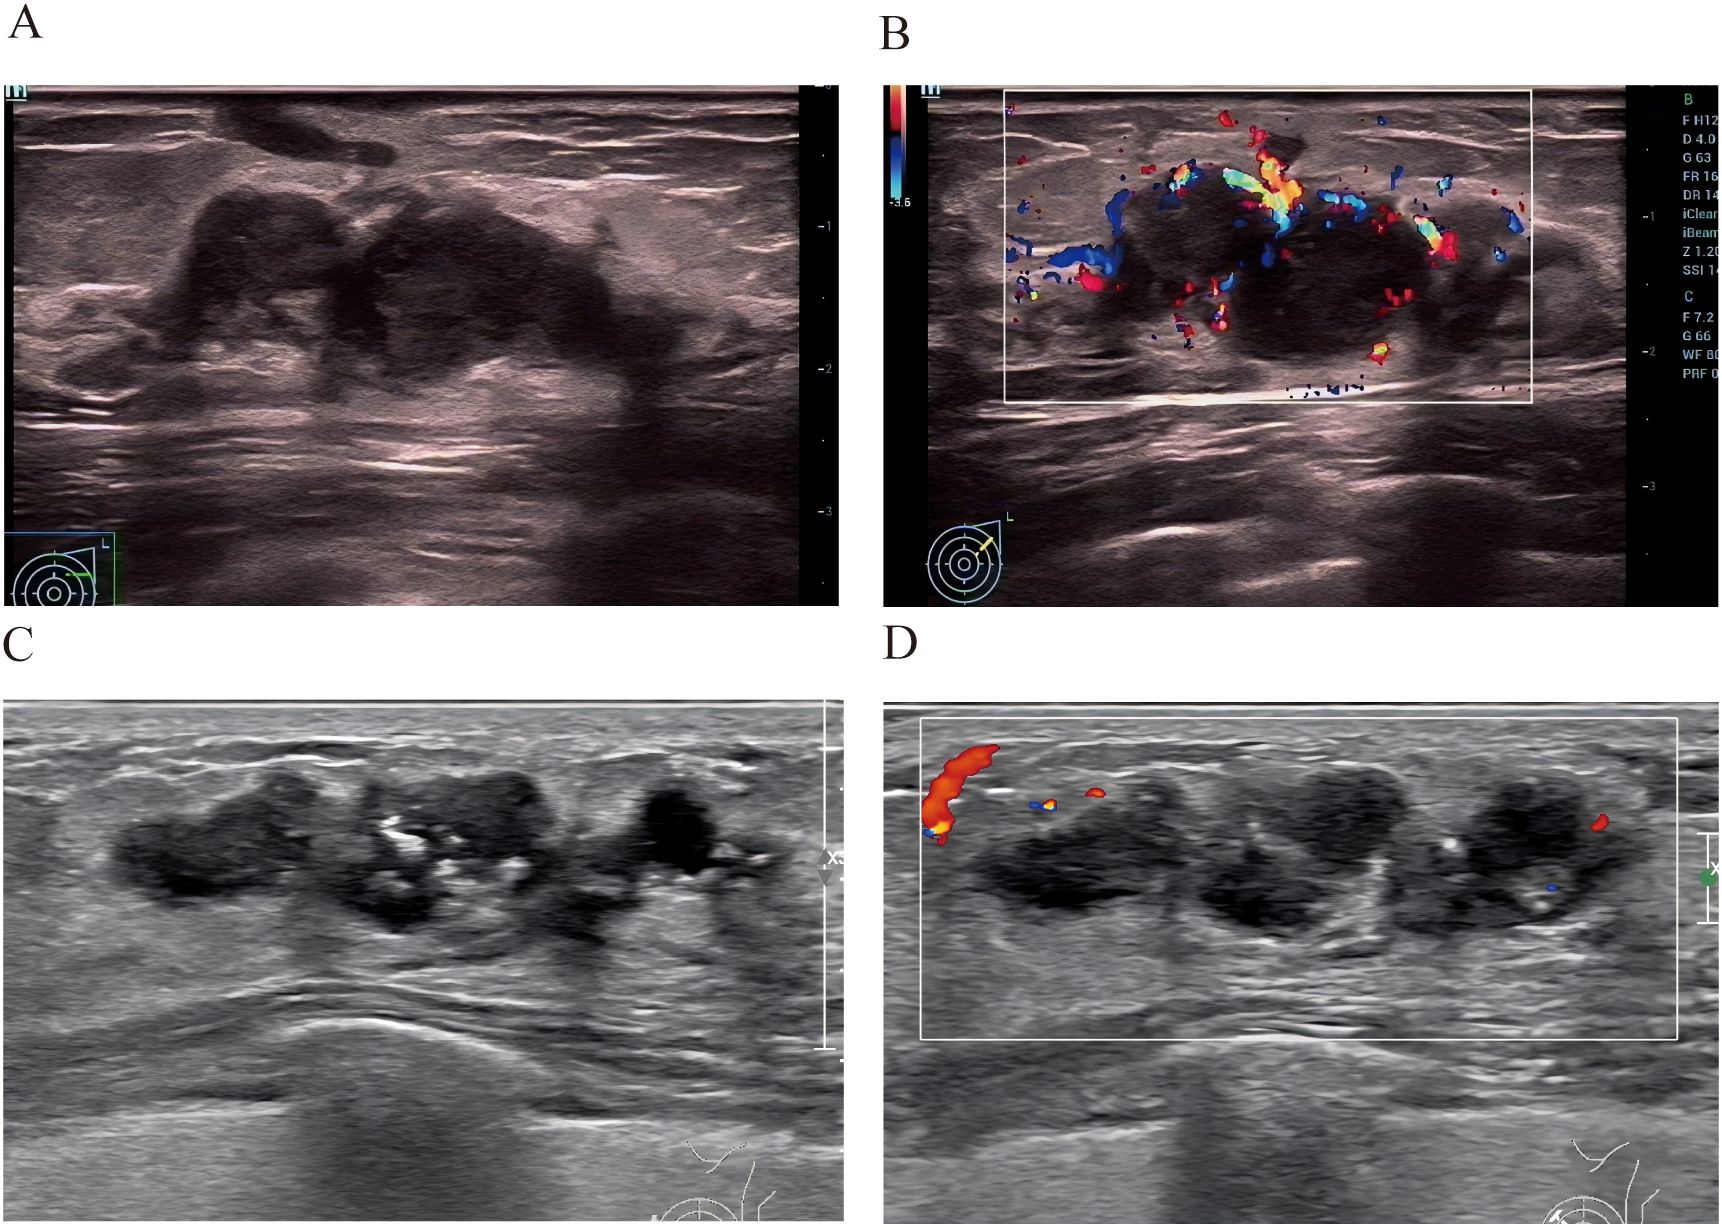

You don't have a Frontiers account ? You can register here

Background: Granulomatous lobular mastitis (GLM) frequently mimics ductal carcinoma in situ (DCIS) in clinical presentation and imaging characteristics, leading to misdiagnosis and unnecessary aggressive interventions. This study aimed to develop and validate a practical nomogram for differentiating GLM from DCIS. Methods: We conducted a retrospective study at Quanzhou First Hospital from January 2020 to April 2025, including 290 patients with histopathologically confirmed GLM (n=128) or DCIS (n=162). Patients were randomly divided into training (n=203) and validation (n=87) sets. Clinical, laboratory, and ultrasound features were analyzed using univariate and multivariate logistic regression to identify independent predictors. A nomogram was constructed and evaluated using receiver operating characteristic (ROC) curves, calibration plots, and decision curve analysis. Results: Six independent predictors were incorporated into the final nomogram: age, lesion size, margin characteristics, microcalcifications, posterior acoustic enhancement, and peri-lesional flow. The nomogram demonstrated excellent discriminative performance with areas under the ROC curve of 0.95 (95% CI: 0.92-0.98) in the training set and 0.93 (95% CI: 0.88-0.98) in the validation set. At optimal thresholds, the model achieved sensitivity of 92% and specificity of 89% in the training set, and 89% and 79% respectively in the validation set. Calibration plots confirmed high predictive accuracy, and decision curve analysis demonstrated substantial clinical benefit across clinically relevant threshold probabilities. Conclusions: This novel nomogram represents a diagnostic tool specifically designed for GLM versus DCIS differentiation. Its reliance on widely available clinical and ultrasound parameters makes it particularly valuable for resource-limited settings, potentially reducing unnecessary biopsies and associated patient morbidity.